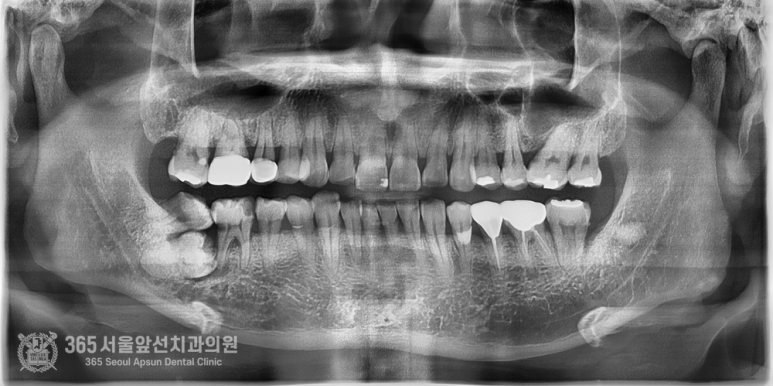

촬영일자:24.05.09 처음 내원 당시 엑스레이 사진입니다. 사진상에서 왼쪽편에 매복된 치아들이 관찰되며, 신경관에 치아뿌리가 닿아 있어서 난이도가 높은 발치로 예상됩니다. 잇몸과 치아의 다양한 문제점들이 섞여있던 상황으로 매우 복잡한 상황입니다.